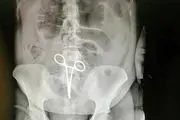

• جا ماندن پنس 22 سانتی داخل بدن زن بیمار!

جا ماندن پنس ۲۲ سانتی داخل بدن زن بیمار!

زن بینوا چند روز بعد ترخیص از بیمارستان در حالیکه نمی توانست دردهای شدید را تحمل کند نزد جراح خود رفت ، جاماندن پنس داخل بدن بیمار با سی تی اسکن روشن شد.